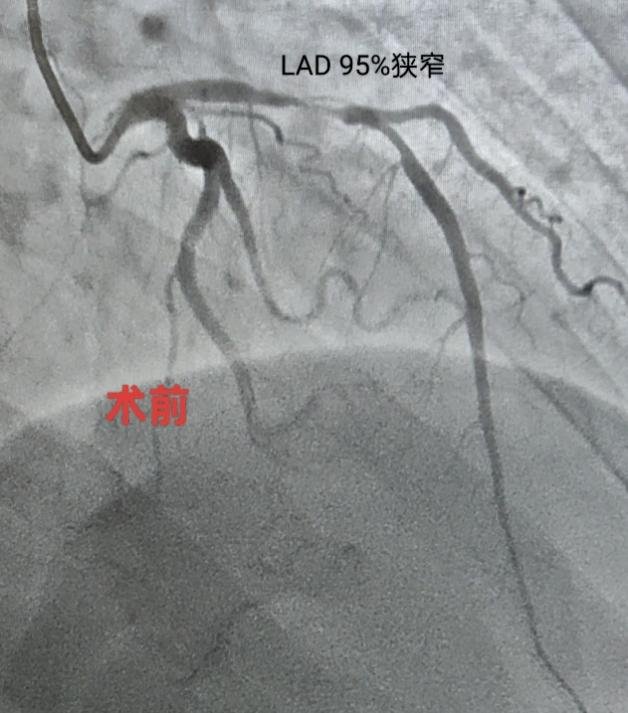

听说要做心脏手术,王女生十分紧张,“总感觉自己得了大病”。魏望江便亲自前去劝解。为了让患者安心,同时确保第一例心脏介入手术顺利开展,魏望江特意邀请北京地坛医院心内科副主任(主持工作)管浩等人讨论病情,在管浩主任的指导下,根据患者情况制定合理的手术和治疗方案。4月16日,由北京地坛医院董茜、郑迪两位专家主刀,徐州医院导管室医护人员参与,为王女士行心脏冠状动脉造影及支架置入术。术后患者恢复良好,无并发症,各项检查指标均在合理范围,即将办理出院。

(术前术后冠状动脉对照)